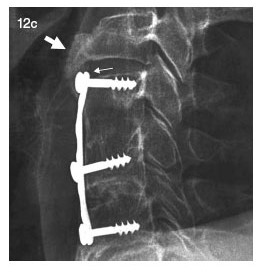

Durante el pase de visita anuncian que harán una disectomía con injerto óseo autólogo y fijación con láminas y tornillos, y yo pido que traduzcan a un idioma entendible para mí.

- Es una operación trabajosa y complicada como todas -afirma Jorgito- te vamos a quitar un pedacito de hueso de la cadera, para ponerlo en la cervical fijado con una lámina y tres tornillos.